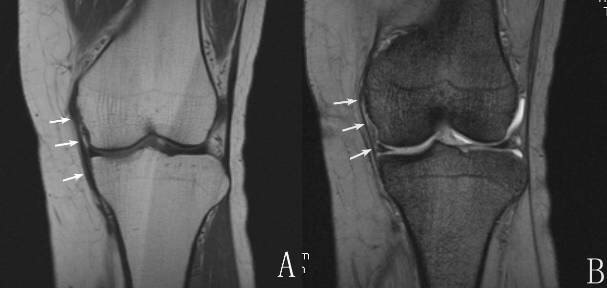

影像学表现MRI上正常副韧带在任何序列均为低信号检查多采用冠状面和横轴面检查侧副韧带损伤MRI上表现为韧带内长T2高信号完全断裂表现为韧带连续性中断或韧带增粗、肿胀、韧带内弥漫性高信号